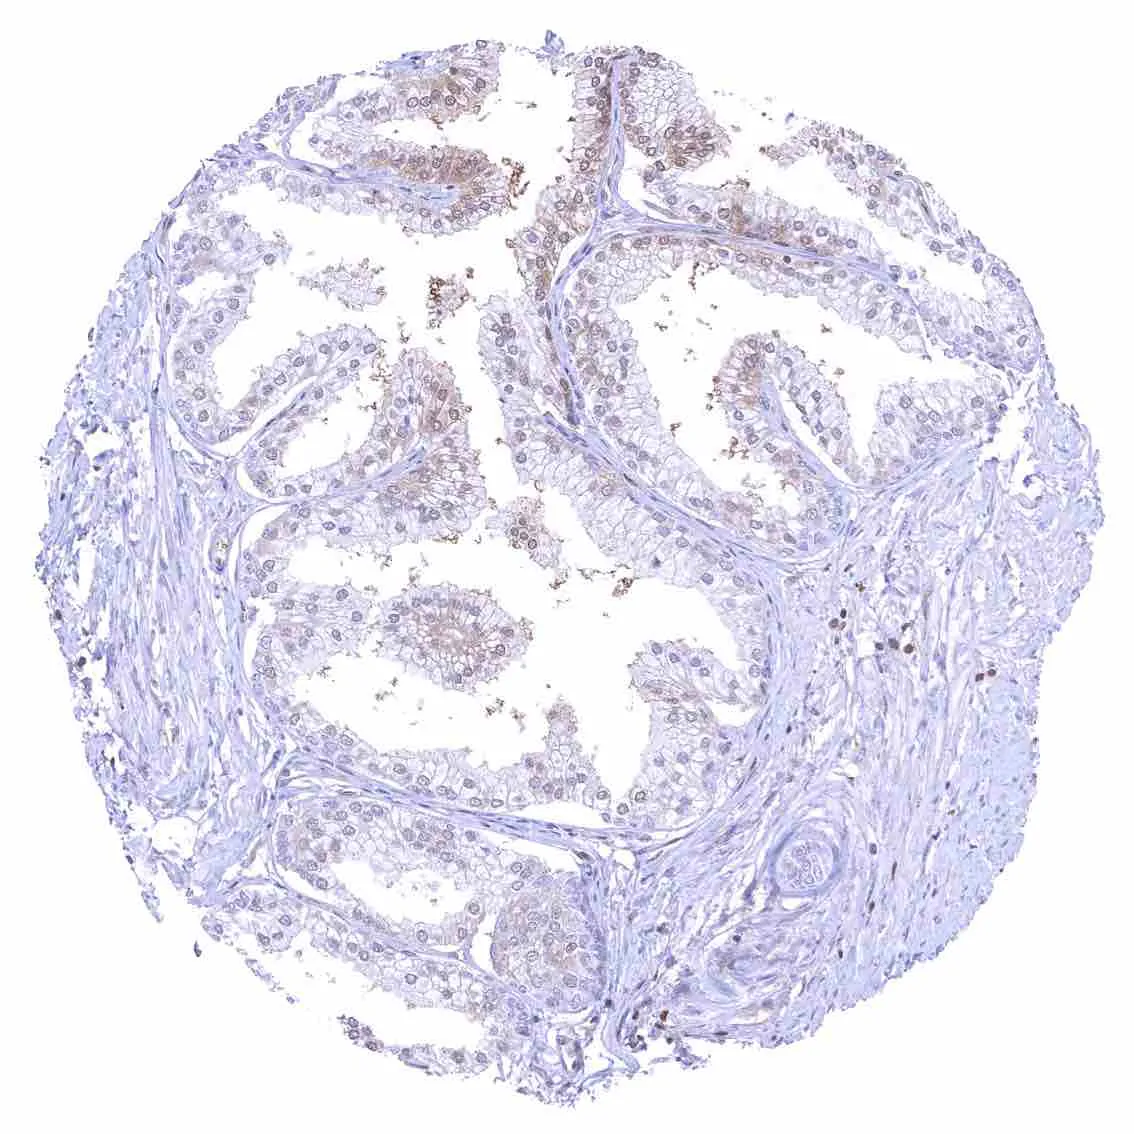

Prostate